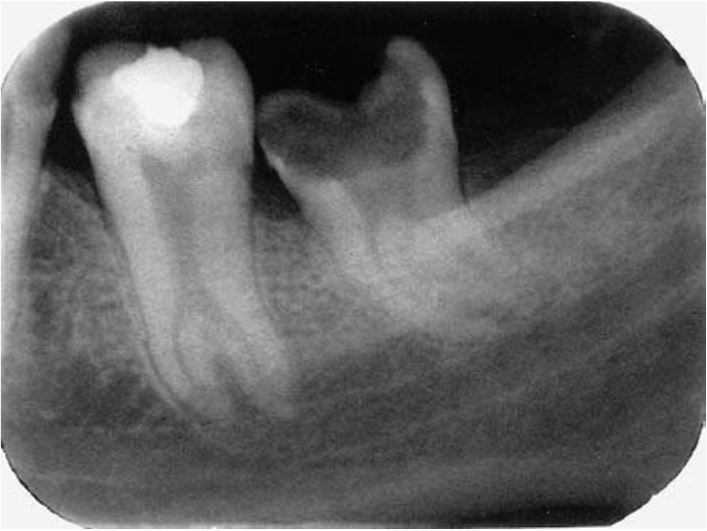

Răng liên trưởng thực sự, xảy ra trong quá trình hoàn tất chân răng, hay gặp giữa R7 và R8 hàm trên khi thiếu chỗ.

Răng liên trưởng khá quan trọng đối với chỉnh nha và nhổ răng. Ví dụ khi nhổ răng khôn có thể gây dịch chuyển R7 liên trưởng. Phẫu thuật cũng không giúp tách rời 2 răng liên trưởng được.